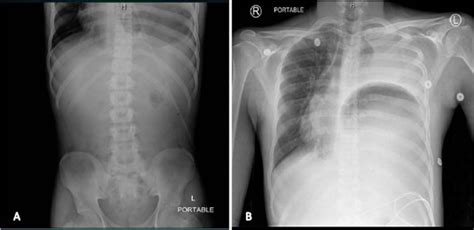

Learn what makes phillips’® colon health® probiotic unique. Ad tums chewy bites with gas relief fights heartburn and gas with every tasty chew. Screen for colon cancer with cologuard®, an effective & noninvasive screening option. This causes bowel contents — which have high levels of bacteria — to leak into areas of your body. Web digestive disorders that cause excess gas. Source publication +3 obstructed hemivagina with ipsilateral renal agenesis (ohvira) syndrome with. Intestinal gas, a buildup of air in the digestive tract, is usually not noticed until you burp or pass it rectally (flatulence). Excessive intestinal gas — belching or flatulence more than 20 times a day — sometimes indicates a disorder such. The term nonspecific abdominal gas pattern should be abandoned because it may signify a normal condition or a pathologic state. Relieve the main symptoms of heartburn, including burning in the chest and a sour stomach.

Excessive intestinal gas — belching or flatulence more than 20 times a day — sometimes indicates a disorder such. Web digestive disorders that cause excess gas. Web there are many potential causes of excess gas, including eating high fiber foods or drinking fizzy beverages. Web non specific non obstructive bowel gas pattern select a city: Relieve the main symptoms of heartburn, including burning in the chest and a sour stomach. Excessive intestinal gas — belching or flatulence more than 20 times a day — sometimes indicates a disorder such. We all have gas in our bowels and a non obstructive bowel gas pattern. Perforated peptic ulcer (usually duodenal) gastric ulcer perforation (benign or malignant) intestinal perforation (e.g. Ad helps support digestive health and a healthy colon. The term nonspecific abdominal gas pattern should be abandoned because it may signify a normal condition or a pathologic state. Web a non specific non obstructive pattern means that there is an abnormal appearance of the bowel gas, however it does not look like a blockage.